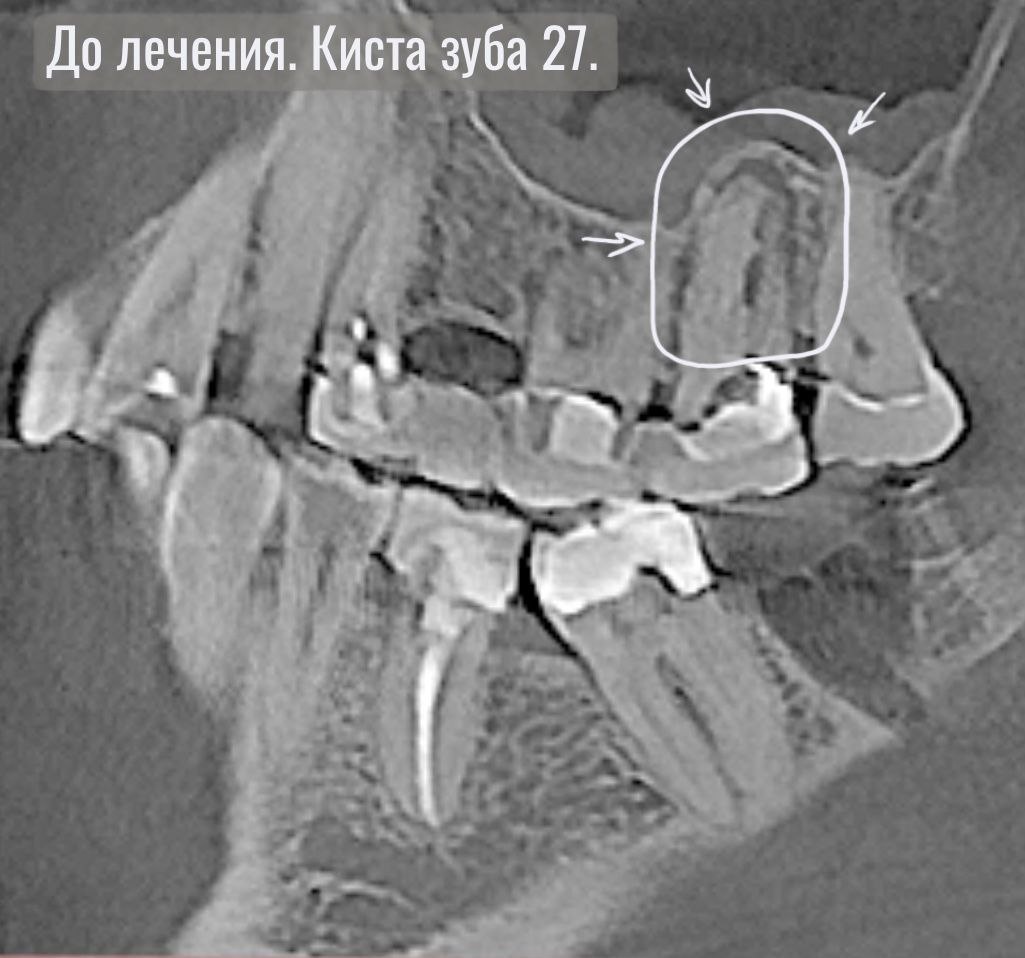

Мы сделали КТ исследование и обнаружили большие кистогранулемы на зубе 26 и 27.

Воспаление в зубе 27